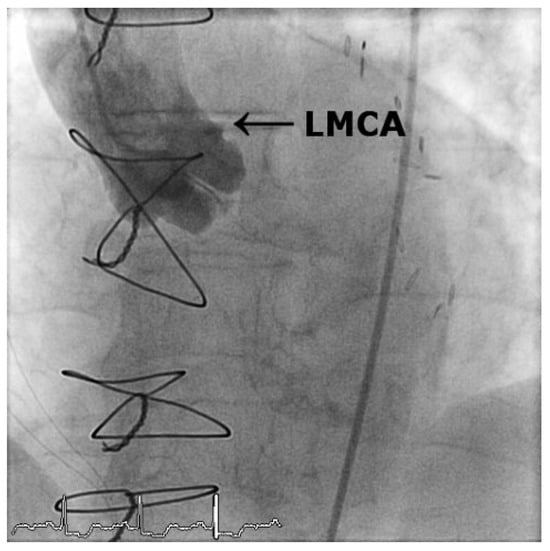

Iatrogenic Left Main Stem Stenosis After Surgical Aortic Valve Replacement

by Jens Robert, David Tüller and Stephan Windecker

Cardiovasc. Med. 2011, 14(3), 101; https://doi.org/10.4414/cvm.2011.01578 - 23 Mar 2011

Surgical aortic valve replacement (SAVR) represents the gold standard in the treatment of symptomatic severe aortic valve stenosis as reflected by the class I indication assigned in the ACC/AHA and ESC guidelines. SAVR effectively relieves symptoms, improves quality of life as well as [...] Read more.

Surgical aortic valve replacement (SAVR) represents the gold standard in the treatment of symptomatic severe aortic valve stenosis as reflected by the class I indication assigned in the ACC/AHA and ESC guidelines. SAVR effectively relieves symptoms, improves quality of life as well as prognosis of affected patients. As with any therapeutic intervention, SAVR is associated with some short and long term adverse events including death, stroke, myocardial infarction, renal failure, bleeding, as well as structural and non-structural valve deterioration. We present two cases of iatrogenic left main stemstenosis within less than one year after SAVR, describe the management and discuss the literature. Full article